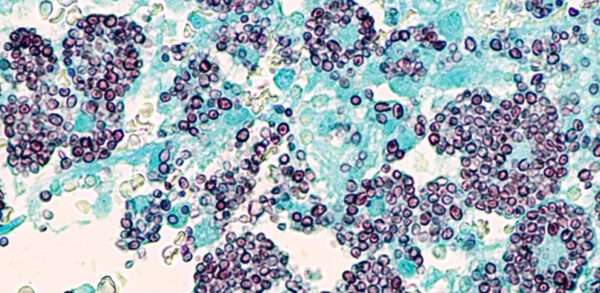

La esporotricosis es una infección micótica crónica que se desarrolla a partir de la inoculación en la piel de hongos pertenecientes al complejo Sporothrix schenckii. Este complejo agrupa varias especies…